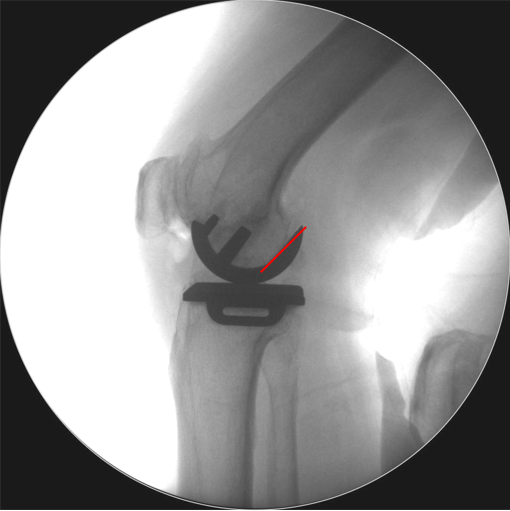

Bearing脱位在正位片上显示股骨与胫骨假体关节面接触,侧位片显示bearing位于关节囊前方或者后方。

病例1:Bearing 前脱位

病例1:Bearing 前脱位的处理